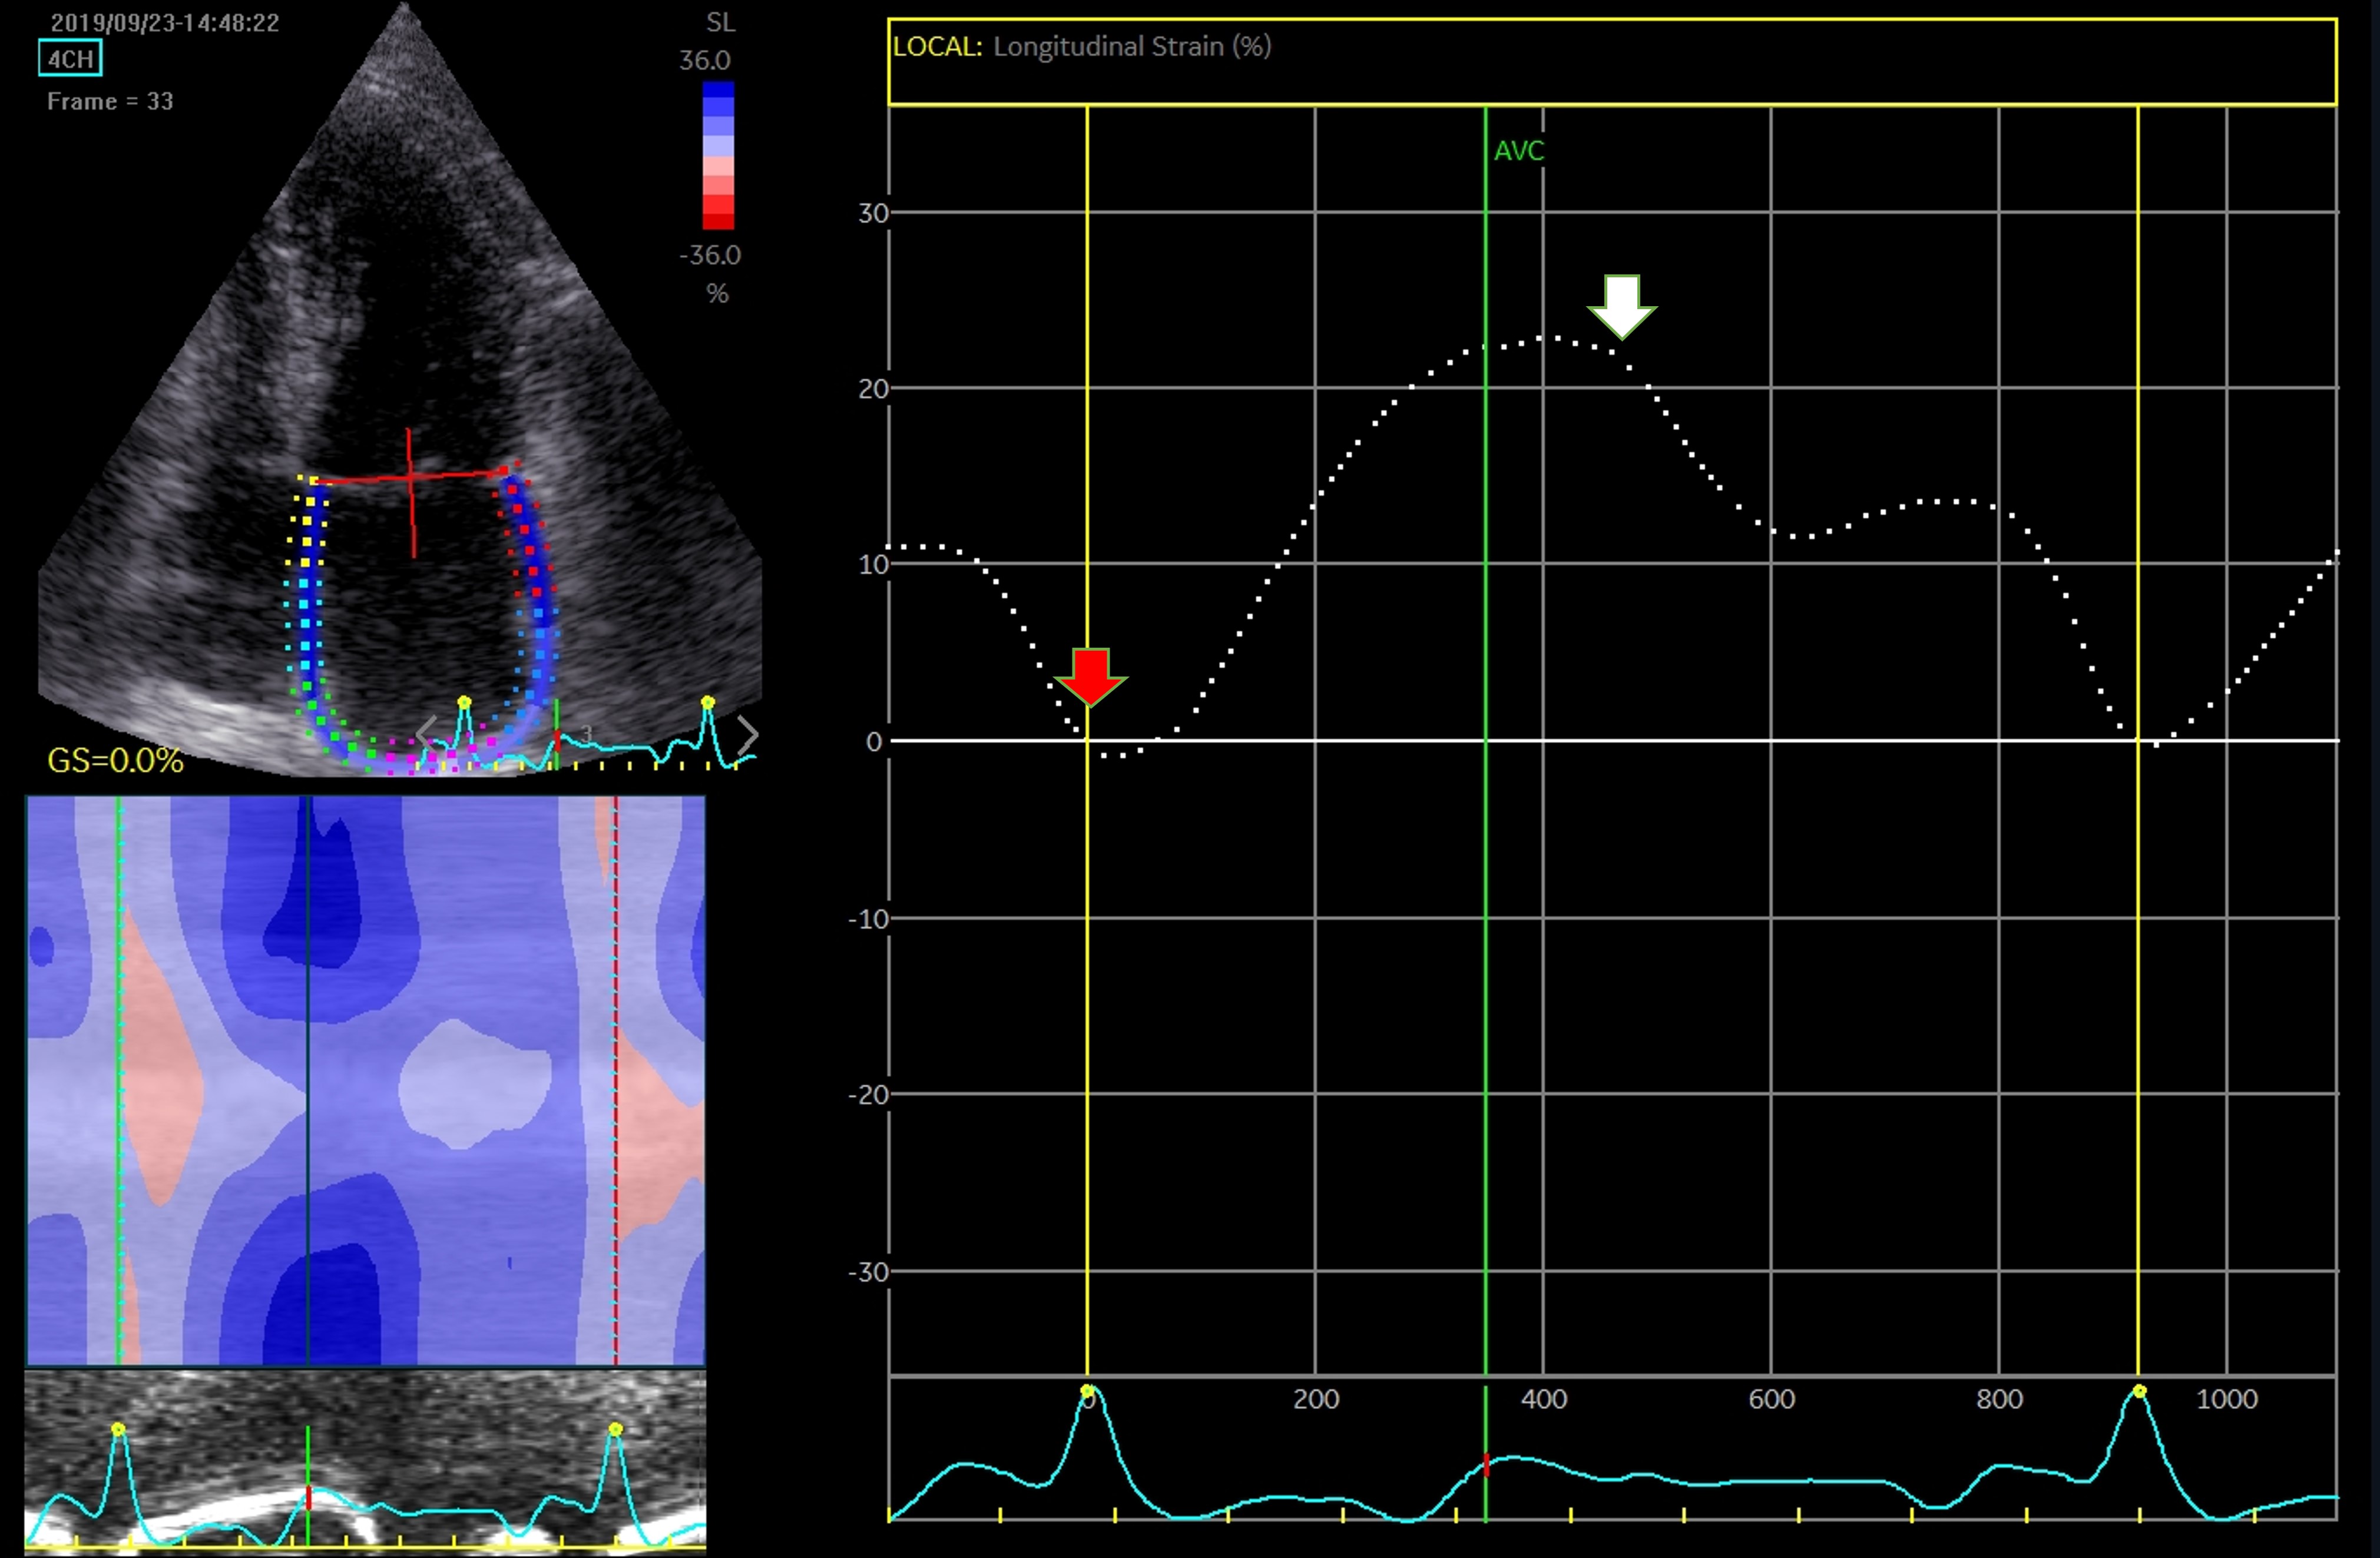

Strain analysis has the advantage of being a semi-automated, angle-independent technique. The need to manually track the LA walls and reposition the region of interest on each segment, makes this investigation time consuming and decreases reproducibility. Until recently, studies relied on a single software, and consensus and interchangeability between different software are still needed. Irrespective of these limitations, atrial strain is validated and correlates with the degree of fibrosis [88]. The assessment can address a 4-chamber view (6 segments) only, or both 4- and 2-chamber views (12 segments), in dedicated optimized views to record a maximized cross-sectional image of the chamber. The recommendations highlight exclusion of pulmonary veins and appendage orifice [53]. Interpretation of LA strain as global strain is advised, while using a single apical 4-chamber view to assess LA longitudinal strain is acceptable. Notably, the interatrial septum is more difficult to visualize. This is the reason why most studies disregarded the interatrial septal deformation and focused on lateral wall movement [89]. The LA septal strain is influenced by its fibromuscular composition and by right atrial pressure. In 2- chamber view, the problem of strain analysis depends on the LA appendage, which often compromises the recognition of speckles and deformation analysis [90]. The measurements may be interpreted using the QRS-complex [53] or the P-wave intervals [91], with similar reproducibility, but better feasibility and shorter time-to-analysis for the former (Figs. 8,9). Moreover, the QRS-complex interval has an advantage when assessing patients with arrhythmias, as AF [92].

Fig. 8.

Fig. 8.Assessment of LA function by speckle tracking echo using the R-R interval – peak systolic LA strain (arrow). Four-chamber view depicting the region of interest (ROI, in the left). The curves represent the mean global LA longitudinal strains. The reference point was set at the onset of the R-wave. The total global strain is positive at the opening of the mitral valve (red arrow). Global strain at atrial contraction is also positive (white arrow). The total global strain is a sum of the negative global strain at atrial contraction (red arrow – at mitral valve closure) and the positive global strain (white arrow – at mitral valve opening).

Fig. 9.

Fig. 9.Strain evaluation of the left atrium using the P-P interval. Four-chamber view depicting the region of interest (ROI, in the left). The curves represent the mean global LA longitudinal strains. The reference point was set at the onset of the P-wave. The total global strain is a sum of the negative global strain at atrial contraction (red arrow – at mitral valve closure) and the positive global strain (white arrow – at mitral valve opening).

The limitations of the method include the location of the LA, reduced signal to noise ratio, a thin wall, and the presence of pulmonary veins and LA appendage. These particularities make the LA strain analysis more difficult and time-consuming compared with left ventricle strain evaluation [90].

LA strain of the reservoir phase (LAS-r) corresponds to LA early diastole (peak atrial longitudinal strain - PALS); LA strain in the conduit phase (LAS-cd) corresponds to LA mid-diastolic emptying with its passive shortenings while LA strain in the contraction phase (LAS-ct) or peak atrial contraction strain (PACS) corresponds to LA systole with active myocardial shortening that produces the atrial contribution to ventricular filling. In normal individuals, the reservoir, passive conduit, and pumping phase account for 40%, 35%, and 25% of left ventricular filling, respectively [90]. There is no single measurement that can be used to determine LA function, and several parameters have been used in clinical studies. Nevertheless, the global function is best reflected by the reservoir strain [53, 54].

Strain measurements, LA reservoir, and conduit strain vary with age. They are significantly lower by the sixth decade, and between genders. During this time, the LA contractile strain improves, as a compensatory mechanism, and this mechanism is predominant in males [93].

Compared to SR patients, in patients with AF, the reservoir and conduit strain are decreased, while the atrial contraction is absent. The alteration of the reservoir function may be detected even before AF development, as a consequence of LA fibrosis and reduced compliance. Reservoir function by LA speckle tracking has an inverse linear relationship to cardiac magnetic resonance late gadolinium enhancement detecting fibrosis, thus evaluation of the function before a procedural approach may be a strong predictor of outcome [47]. After SR restoration, reverse atrial remodeling is reflected by an increase in LA reservoir function and passive conduit strain [94]. This improvement in the LA reservoir function may be approached as a marker of a successful outcome and could show its value in the early recognition of patients with AF recurrences [95].

A reduced LA active pump function independently predicts new-onset AF [96],

while the LA strain is strongly associated with AF recurrences after ablation

[97, 98] and may even predict evolution toward non-paroxysmal episodes [37].